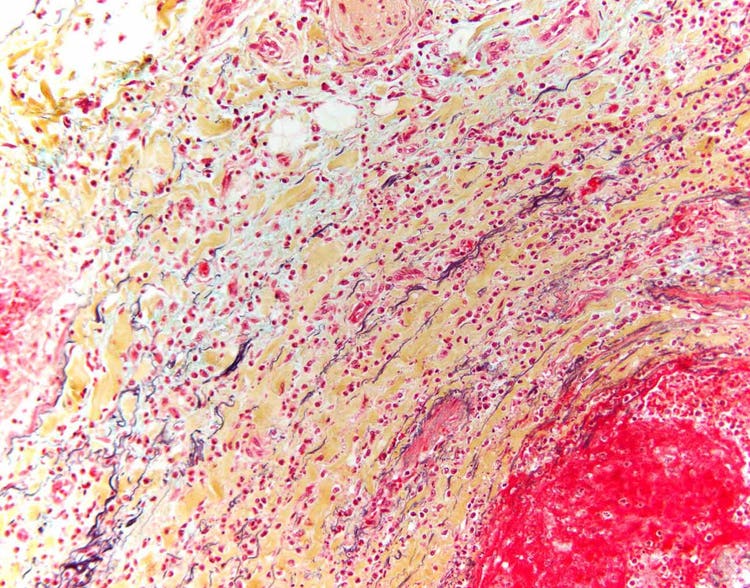

Coupe d’une artère humaine avec une coloration au pentachrome de Movat, qui utilise cinq colorants différents pour mettre en évidence les différents éléments de l’anatomie subcellulaire. Par exemple, les fibres élastiques de la paroi de l’artère, qui donnent la résistance et la résilience aux vaisseaux sanguins, apparaissent en noir lorsqu’elles sont colorées au pentachrome. Image acquise avec un microscope BX43 d’Olympus équipé d’une caméra DP26. Image reproduite avec l’aimable autorisation de Marianne Hamel.